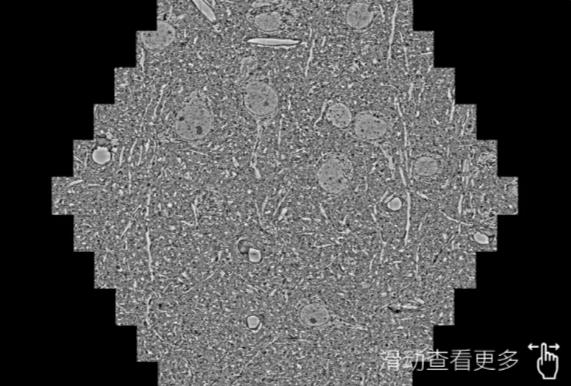

鼠脑切片。左图使用北京蔡司北京扫描电镜MultiSEM706对165μmx143pm面积区域成像,耗时仅需1.5秒。右图为鼠脑切片中30μm区域放大效果。样品由芝加哥大学B.Kasthuri提供。